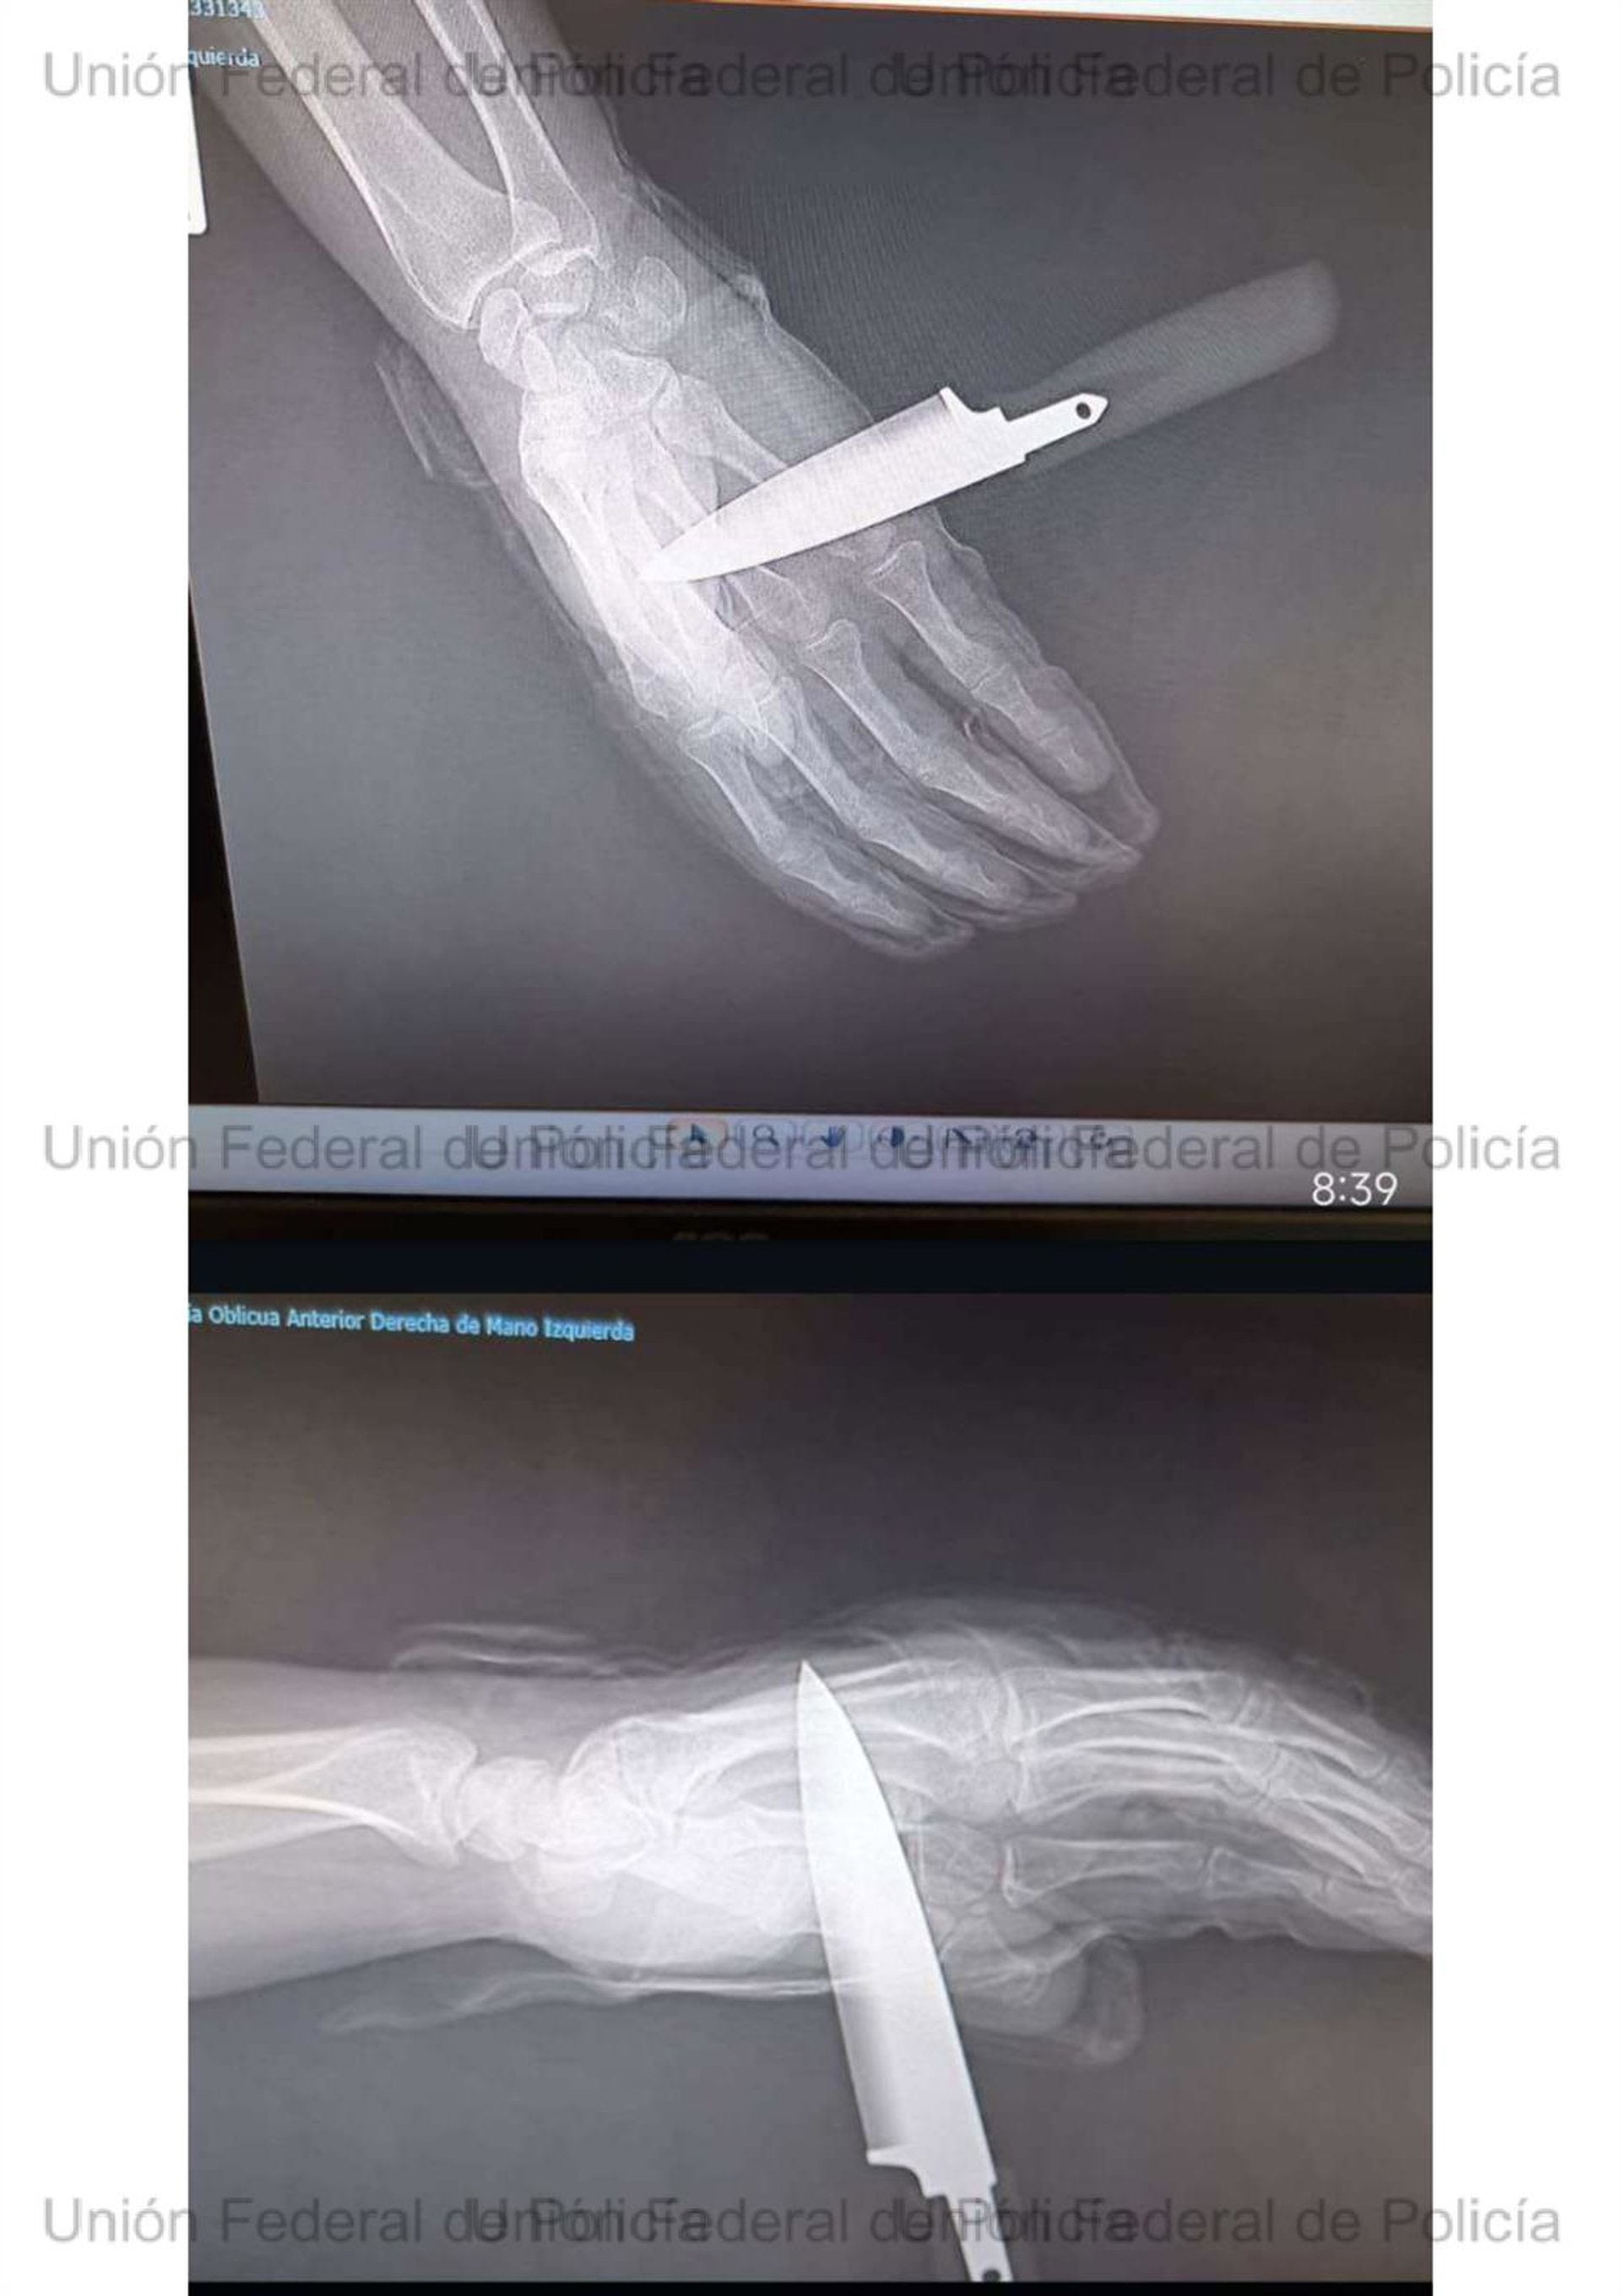

Un agente de la Policía Nacional, apuñalado en Baza durante una intervención familiar

Según la Unión Federal de Policía, el chaleco antibalas evitó una tragedia mayor en un suceso que vuelve a evidenciar los riesgos a los que se enfrentan los agentes.